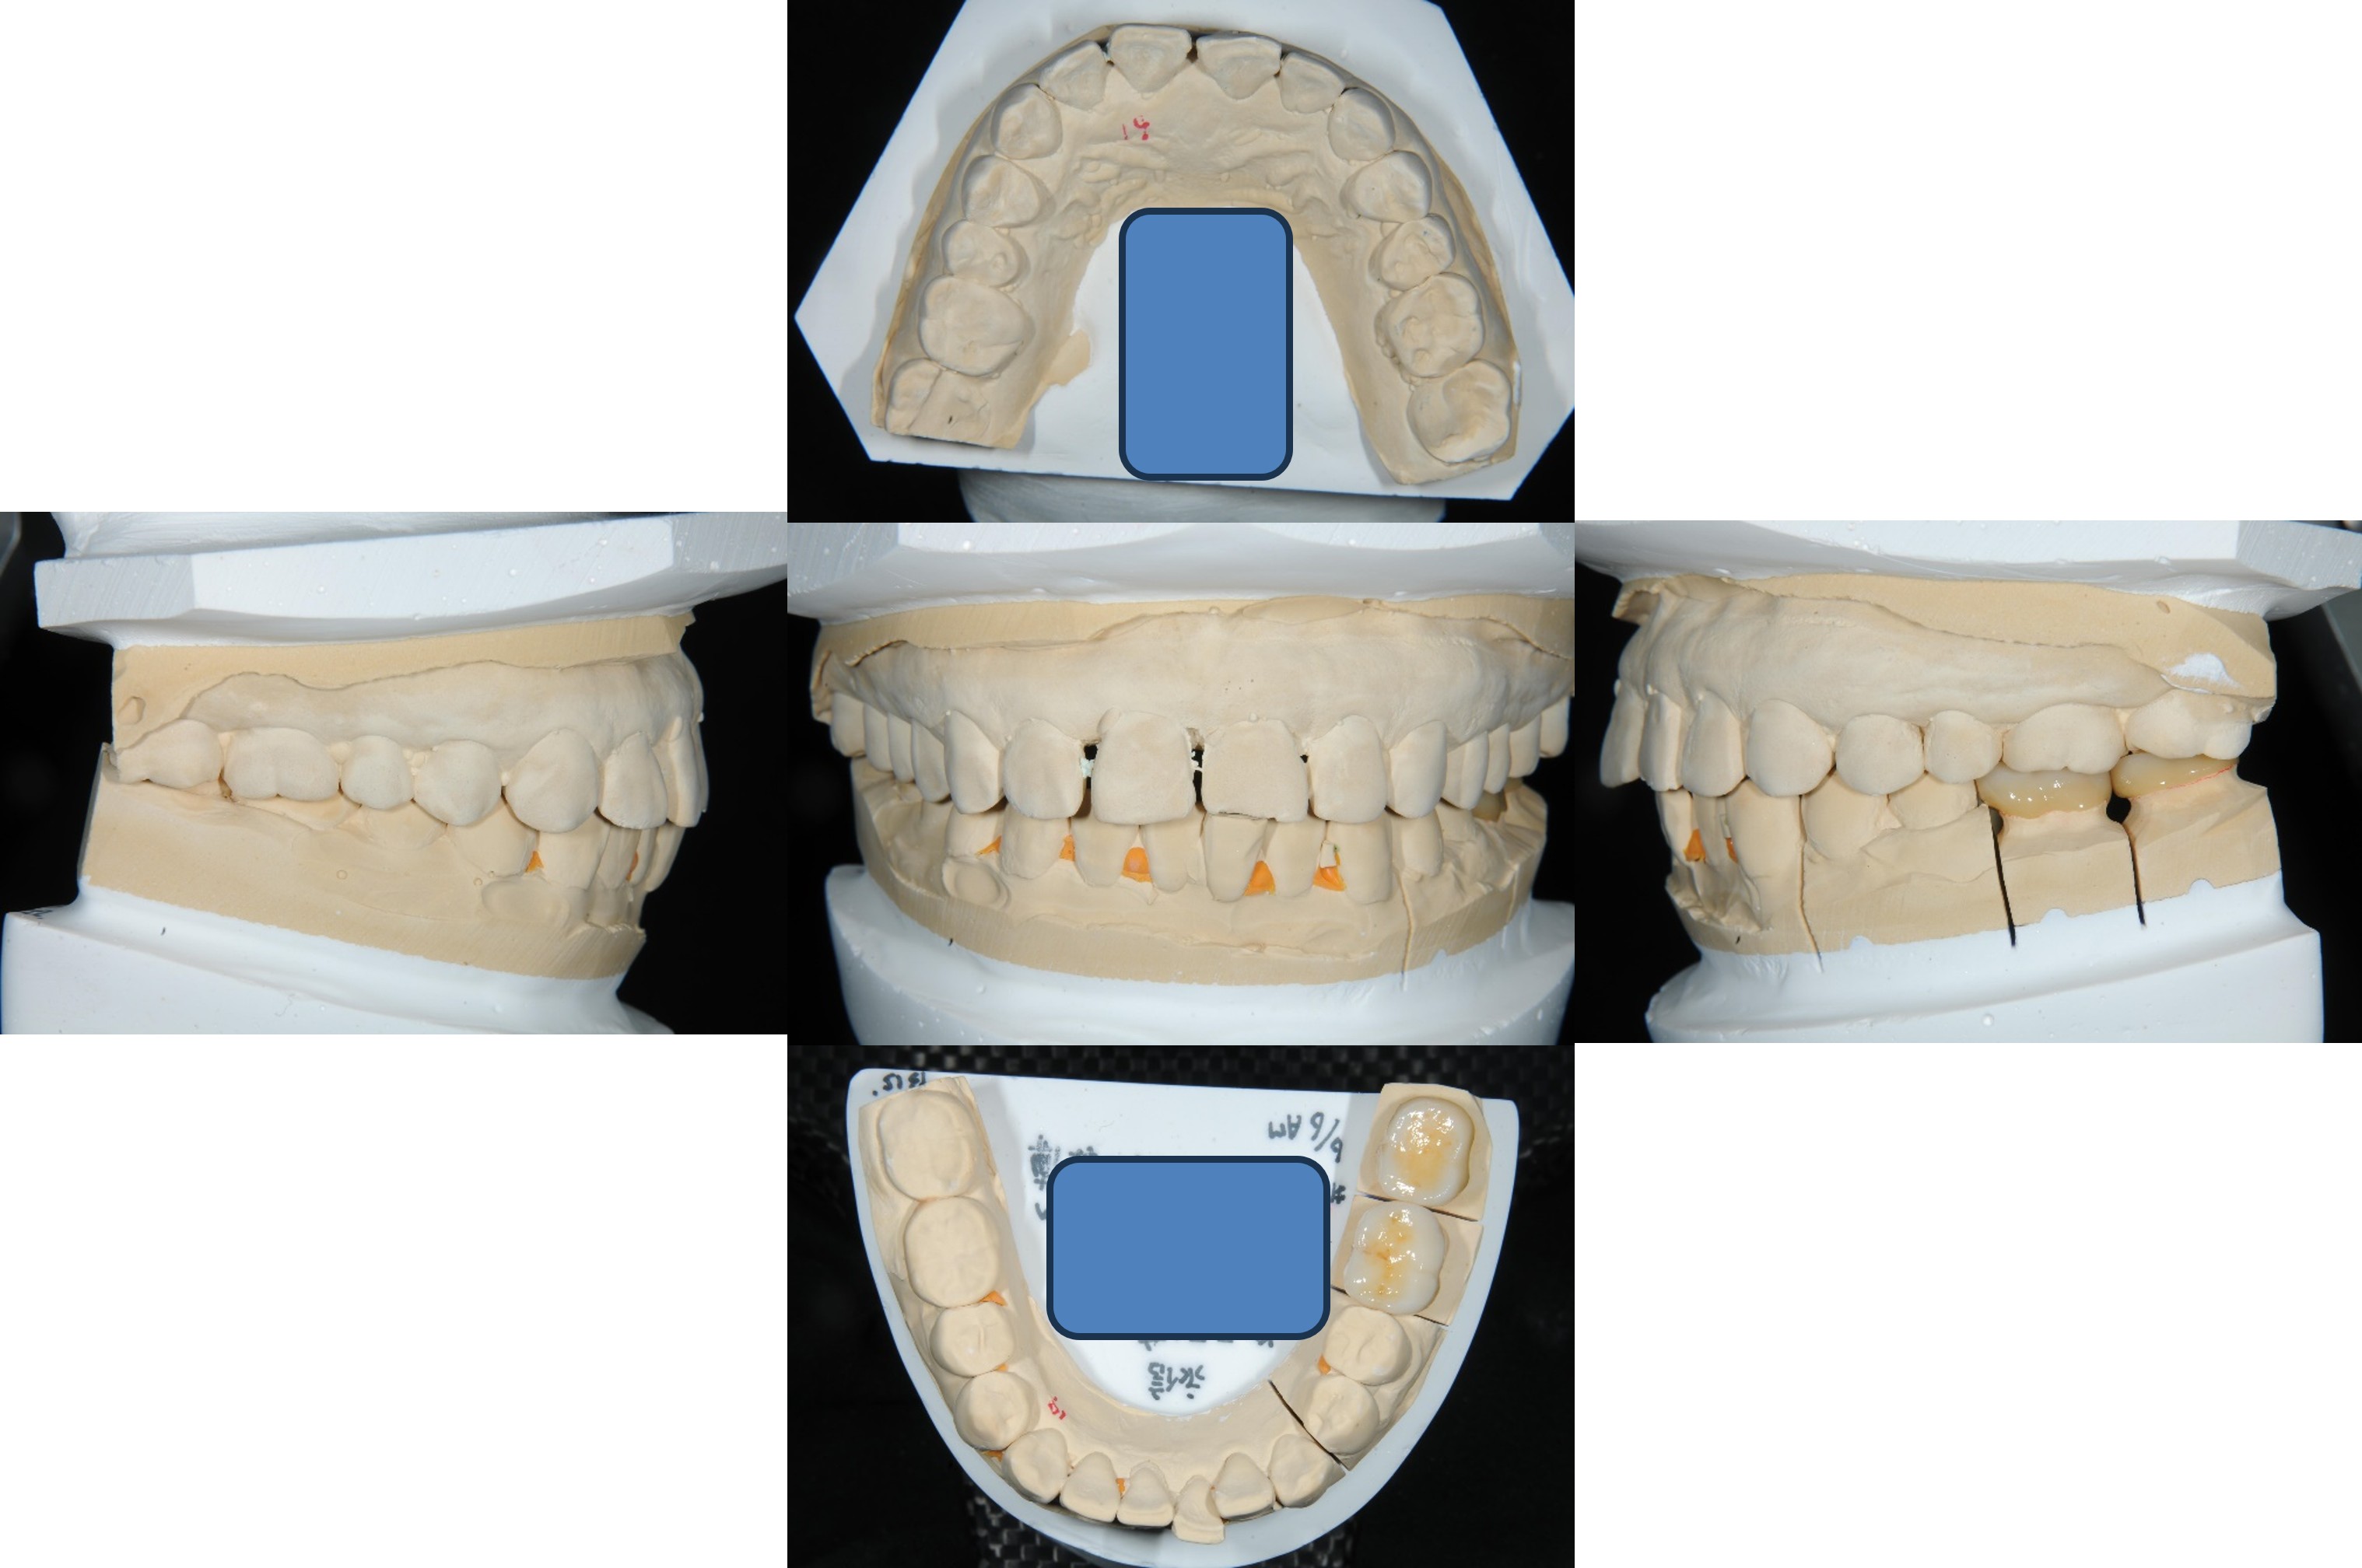

面弓取得、上咬合器

技師於咬合器製作全瓷冠